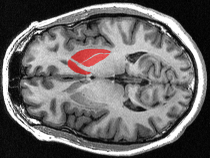

Prúžkované teleso alebo striatum je hlboká oblasť sivej hmoty vnútri hemisfér koncového mozgu a považuje sa za akési ústredie pre rozhodovanie a rozvoj rôznych závislostí. Tímu vedcov z Karolinska Institutet vo Švédsku pod vedením Konstantinosa Meletisa sa podarilo na myšiach vizualizovať organizáciu rôznych opioidných ostrovov… pokračuj